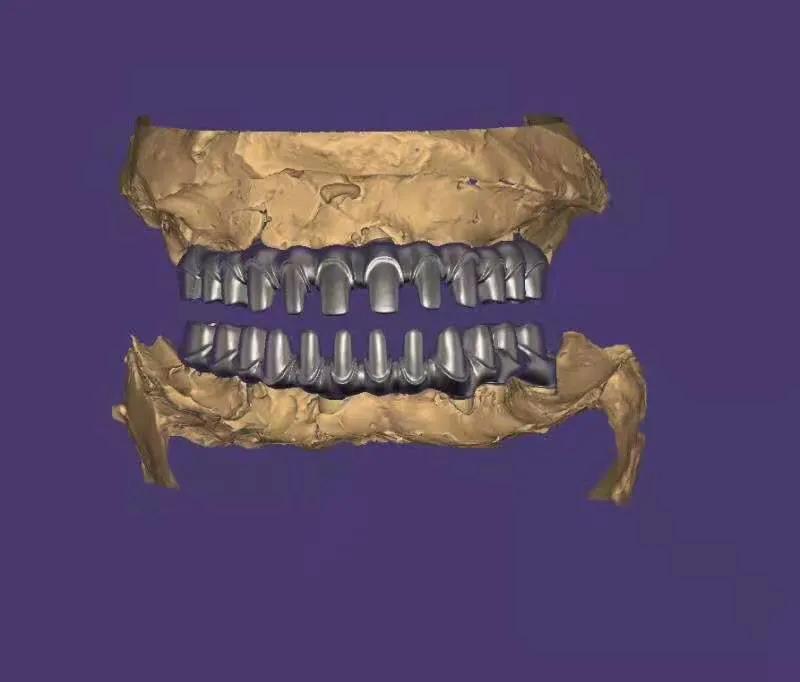

典型的負重,All-On-4。

這就是傳說中的當天戴牙當天吃飯,網(wǎng)上到處宣傳的就是這種種植方法。但是不是每一個人都能做這個,All-on-4一般需要預約,醫(yī)生種植完畢,技師馬上開始取模做牙,大概5小時左右就可以戴上臨時牙回家吃飯了,休息一兩天,正常吃飯是沒問題的。

2. 還有一個問題就是骨件,不是每個人都可以做。骨頭太差,只能做常規(guī)的種植,等3-6個月戴牙,可能更久,中間只能用臨時牙過度。負重開始戴的也是臨時牙,但是這個臨時牙和常規(guī)島臨時牙不一樣,咬合力挺好